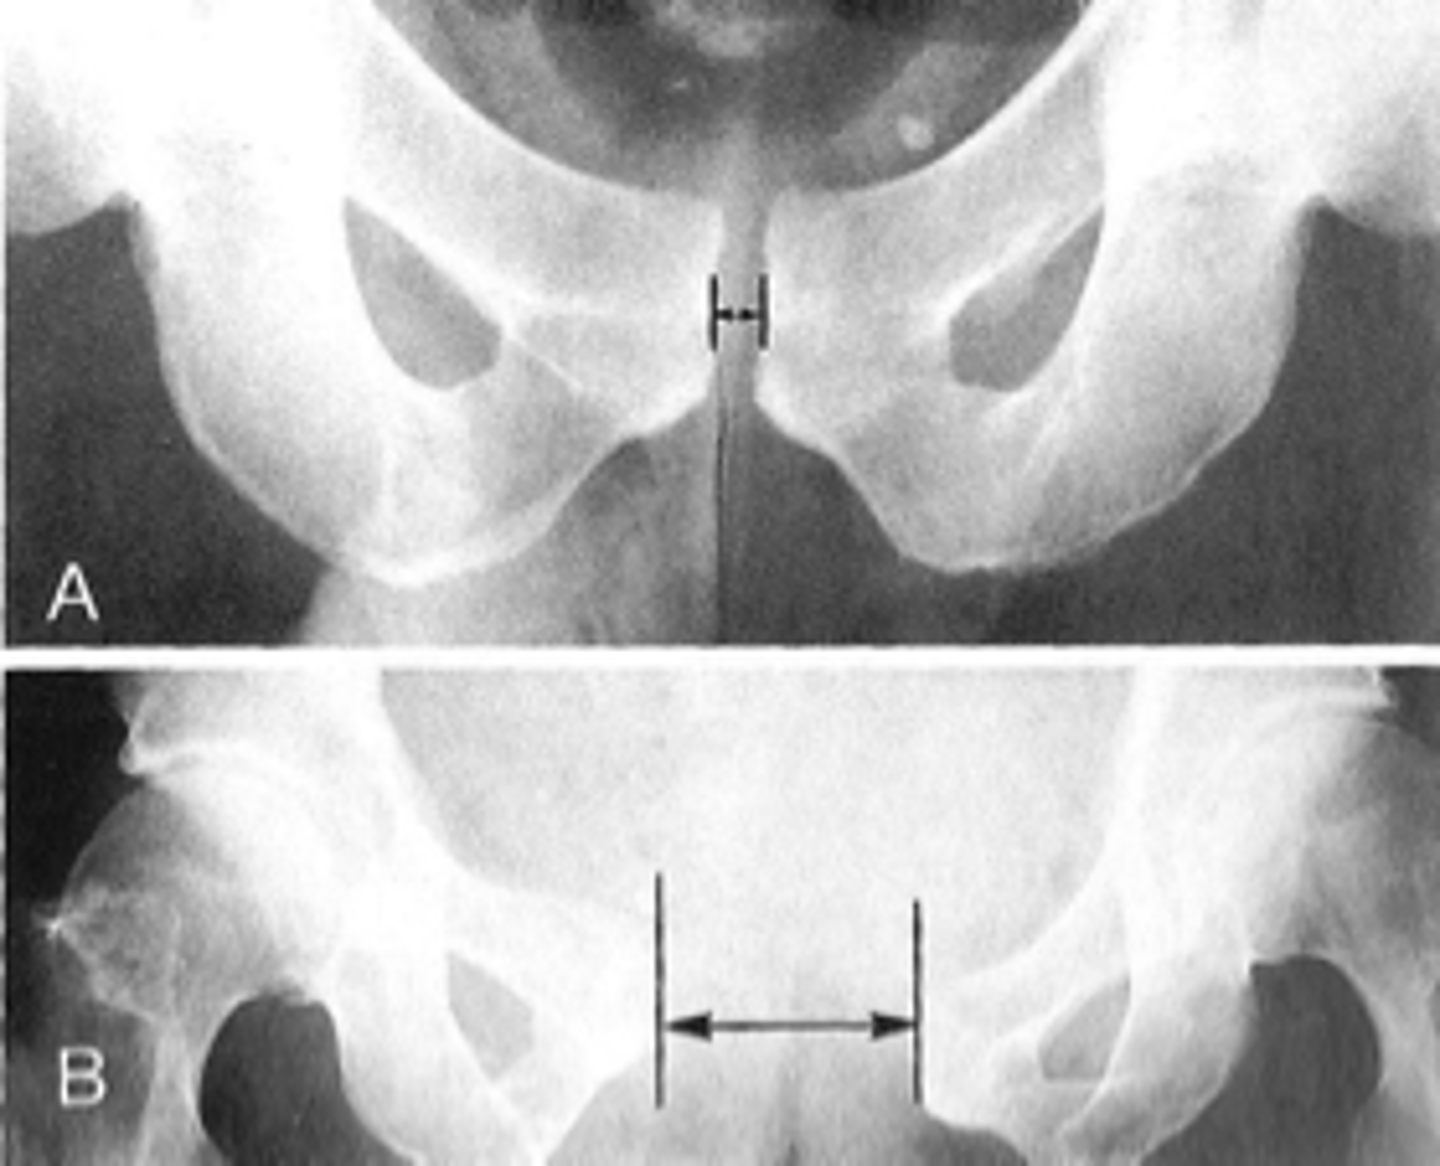

- AP pelvis

- Frog-leg pelvis

State the standard bilateral pelvis projections

AP pelvis

ID standard bilateral pelvis projection

Frog-leg pelvis

Pubic symphysis

ID 1

<p>ID 1</p>

Left femoroacetabular joint

ID 2 (joint)

<p>ID 2 (joint)</p>

Symphysis pubis width

ID measurement

What view is used to see the symphysis pubis width?

Distance between opposing articular surfaces

Symphysis pubis width landmarks

8 mm

Maximum symphysis pubis width measurement in adults

10 mm

Maximum symphysis pubis width measurement in children

Pregnancy/postpartum

The symphysis pubis width may be larger in _____

Diastasis

Clinical significance of a widened symphysis pubis